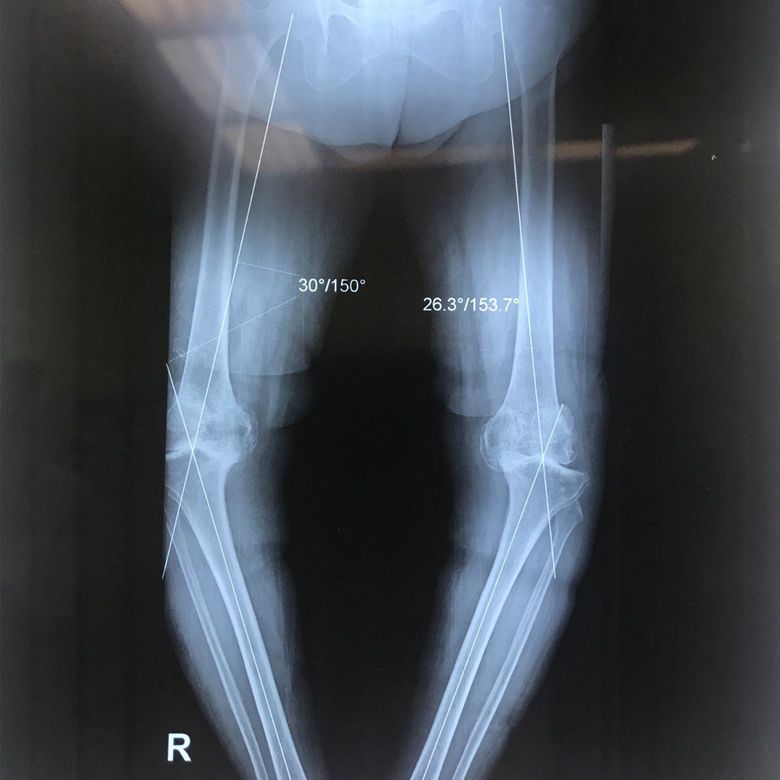

Axial deviation of the knee

Axial deviation of the knee is one of the structural disorders of the knee and can be seen in the form of a bracketed or crossed knee.